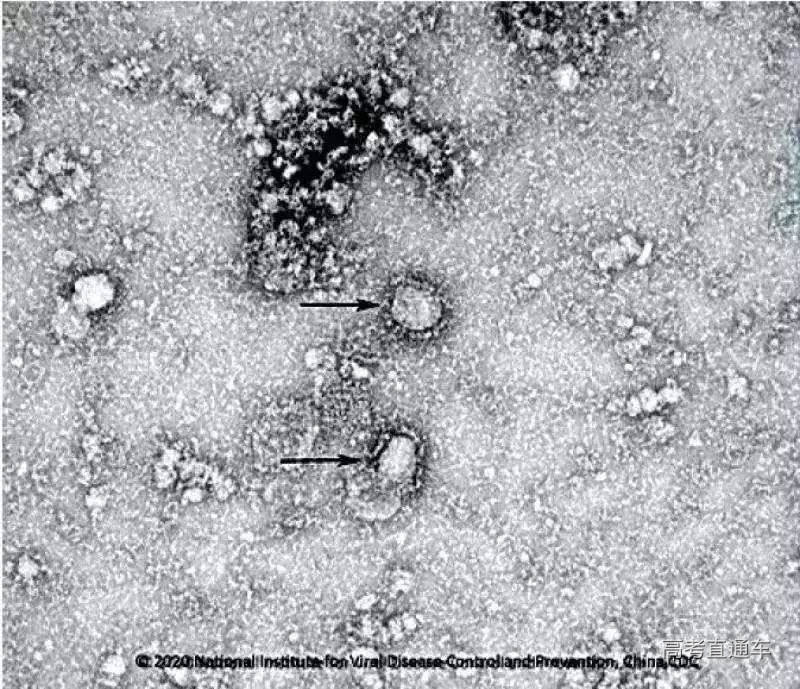

中国疾控中心成功分离我国首株新型冠状病毒毒种:

国家病原微生物资源库于2020年1月24日发布了由中国疾病预防控制中心病毒病预防控制所成功分离的我国第一株病毒毒种信息及其电镜照片、新型冠状病毒核酸检测引物和探针序列等国内首次发布的重要权威信息,并提供共享服务,链接:http://nmdc.cn/#/nCoV。

什么是冠状病毒:

冠状病毒是一类主要引起呼吸道、肠道疾病的病原体。这类病毒颗粒的表面有许多规则排列的突起,整个病毒颗粒就像一顶帝王的皇冠,因此得名“冠状病毒”。

病毒的实质是蛋白质外壳加上核酸,且只能含有一种核酸,DNA或者RNA。根据核酸的类型我们又将病毒分为RNA病毒(如sars、HIV……)和DNA病毒(如乙肝病毒)。而冠状病毒之所以叫做冠状病毒,是因为它在电子显微镜下围了一圈华丽的凸起,好似戴了冠冕,这个冠冕,就是冠状病毒感染宿主的诀窍:每一个凸起,都是一粒“棒状糖蛋白”,就是一根根火柴似的东西。